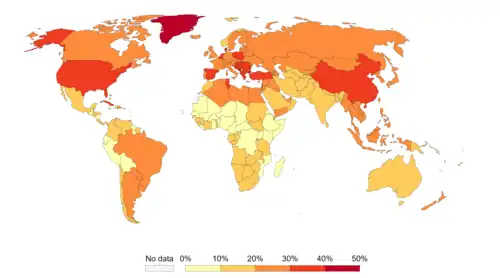

Infection

Worldwide, approximately 18% of cancer deaths are related to infectious diseases.[3] This proportion ranges from a high of 25% in Africa to less than 10% in the developed world.[3] Viruses[69] are the usual infectious agents that cause cancer but bacteria and parasites may also play a role. Oncoviruses (viruses that can cause human cancer) include: